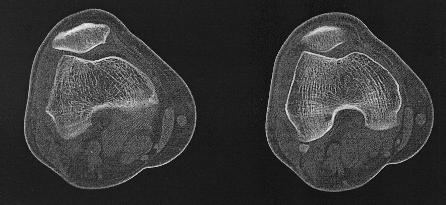

CT van het skelet

Ct knie 3D reconstructieCT Knie

Een Ct-scan van het skelet wordt uitgevoerd wanner er een verdere evaluatie nodigs van een lestel dat gezien is op een klasieke foto. Denk aan fracturen, luxaties e.d., maar ook aan metastasen, arthrose,...Zo kan het bijvoorbeeld zijn dat een letsle niet duidelijk genoeg voorkomt op de foto's endat er dus twijfel bestaat. Maar ook kan het zijn dat een CT-scan noodzaklijk is om een duidelijk beeld te verkrijgen van een uitgebreide fractuur, om verder behandeling te bepalen.

Dankzij de moderne computertechnieken is het niet allen mogelijk om axiale beelden te maken. (lees schijfjes dwars op het lichaam) Maar ook om die beelden te reconstrueren tot een 3D-model. Dit geeft vaak een duidelijk beeld van het bot, en zijn letsel.